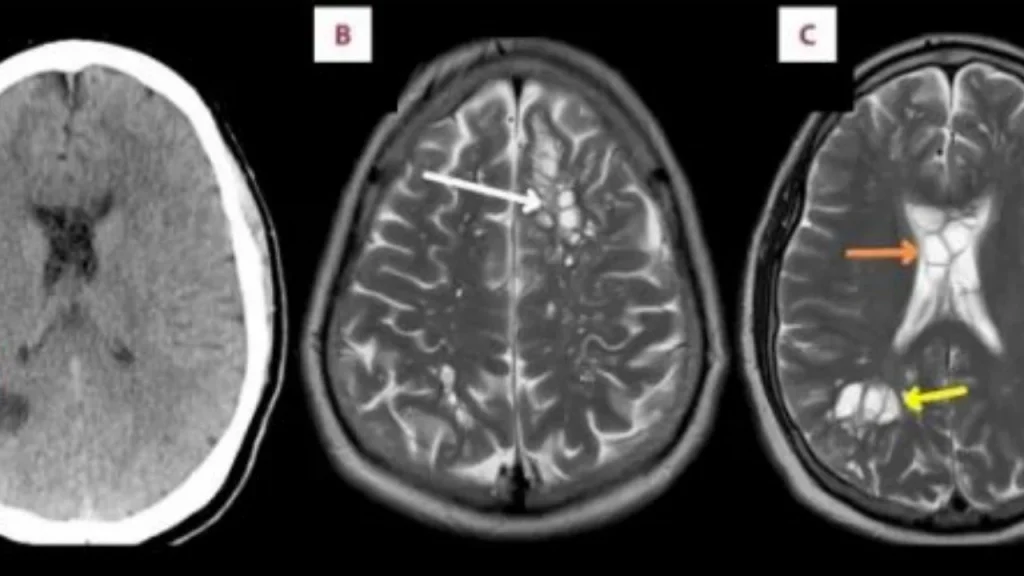

Një burrë nga Florida shkoi në spital sepse vuante nga migrena e rëndë që po përkeqësohej me kalimin e kohës. Ai ishte 52 vjeç dhe i kishte përjetuar këto dhimbje koke çdo javë. Mjekët fillimisht menduan se ai kishte cista të lindura neurogliale pasi panë një masë në një skanim CT. Megjithatë, testet e mëtejshme, duke përfshirë një MRI, zbuluan se masa ishte në të vërtetë larva e krimbit në trurin e tij. Burri nuk e kishte idenë. Pacienti u shtrua në spital, ku testet shtesë konfirmuan se masat nuk ishin ciste, por larva. Një raport i botuar në American Journal of Case Reports deklaroi se antitrupi i cisticerkozës IgG Cysts u kthye pozitiv, duke konfirmuar dyshimin për neurocisticerkozë. Sipas CDC-së, neurocisticerkoza është një infeksion parazitar i parandalueshëm i shkaktuar nga cistat larva të krimbit të derrit, Taenia solium. Këto kiste larva mund të infektojnë pjesë të ndryshme të trupit, duke çuar në një gjendje të quajtur cisticerkozë. Kur kistet e larvave prekin trurin, quhet neurocisticerkozë, e cila mund të rezultojë në konvulsione.